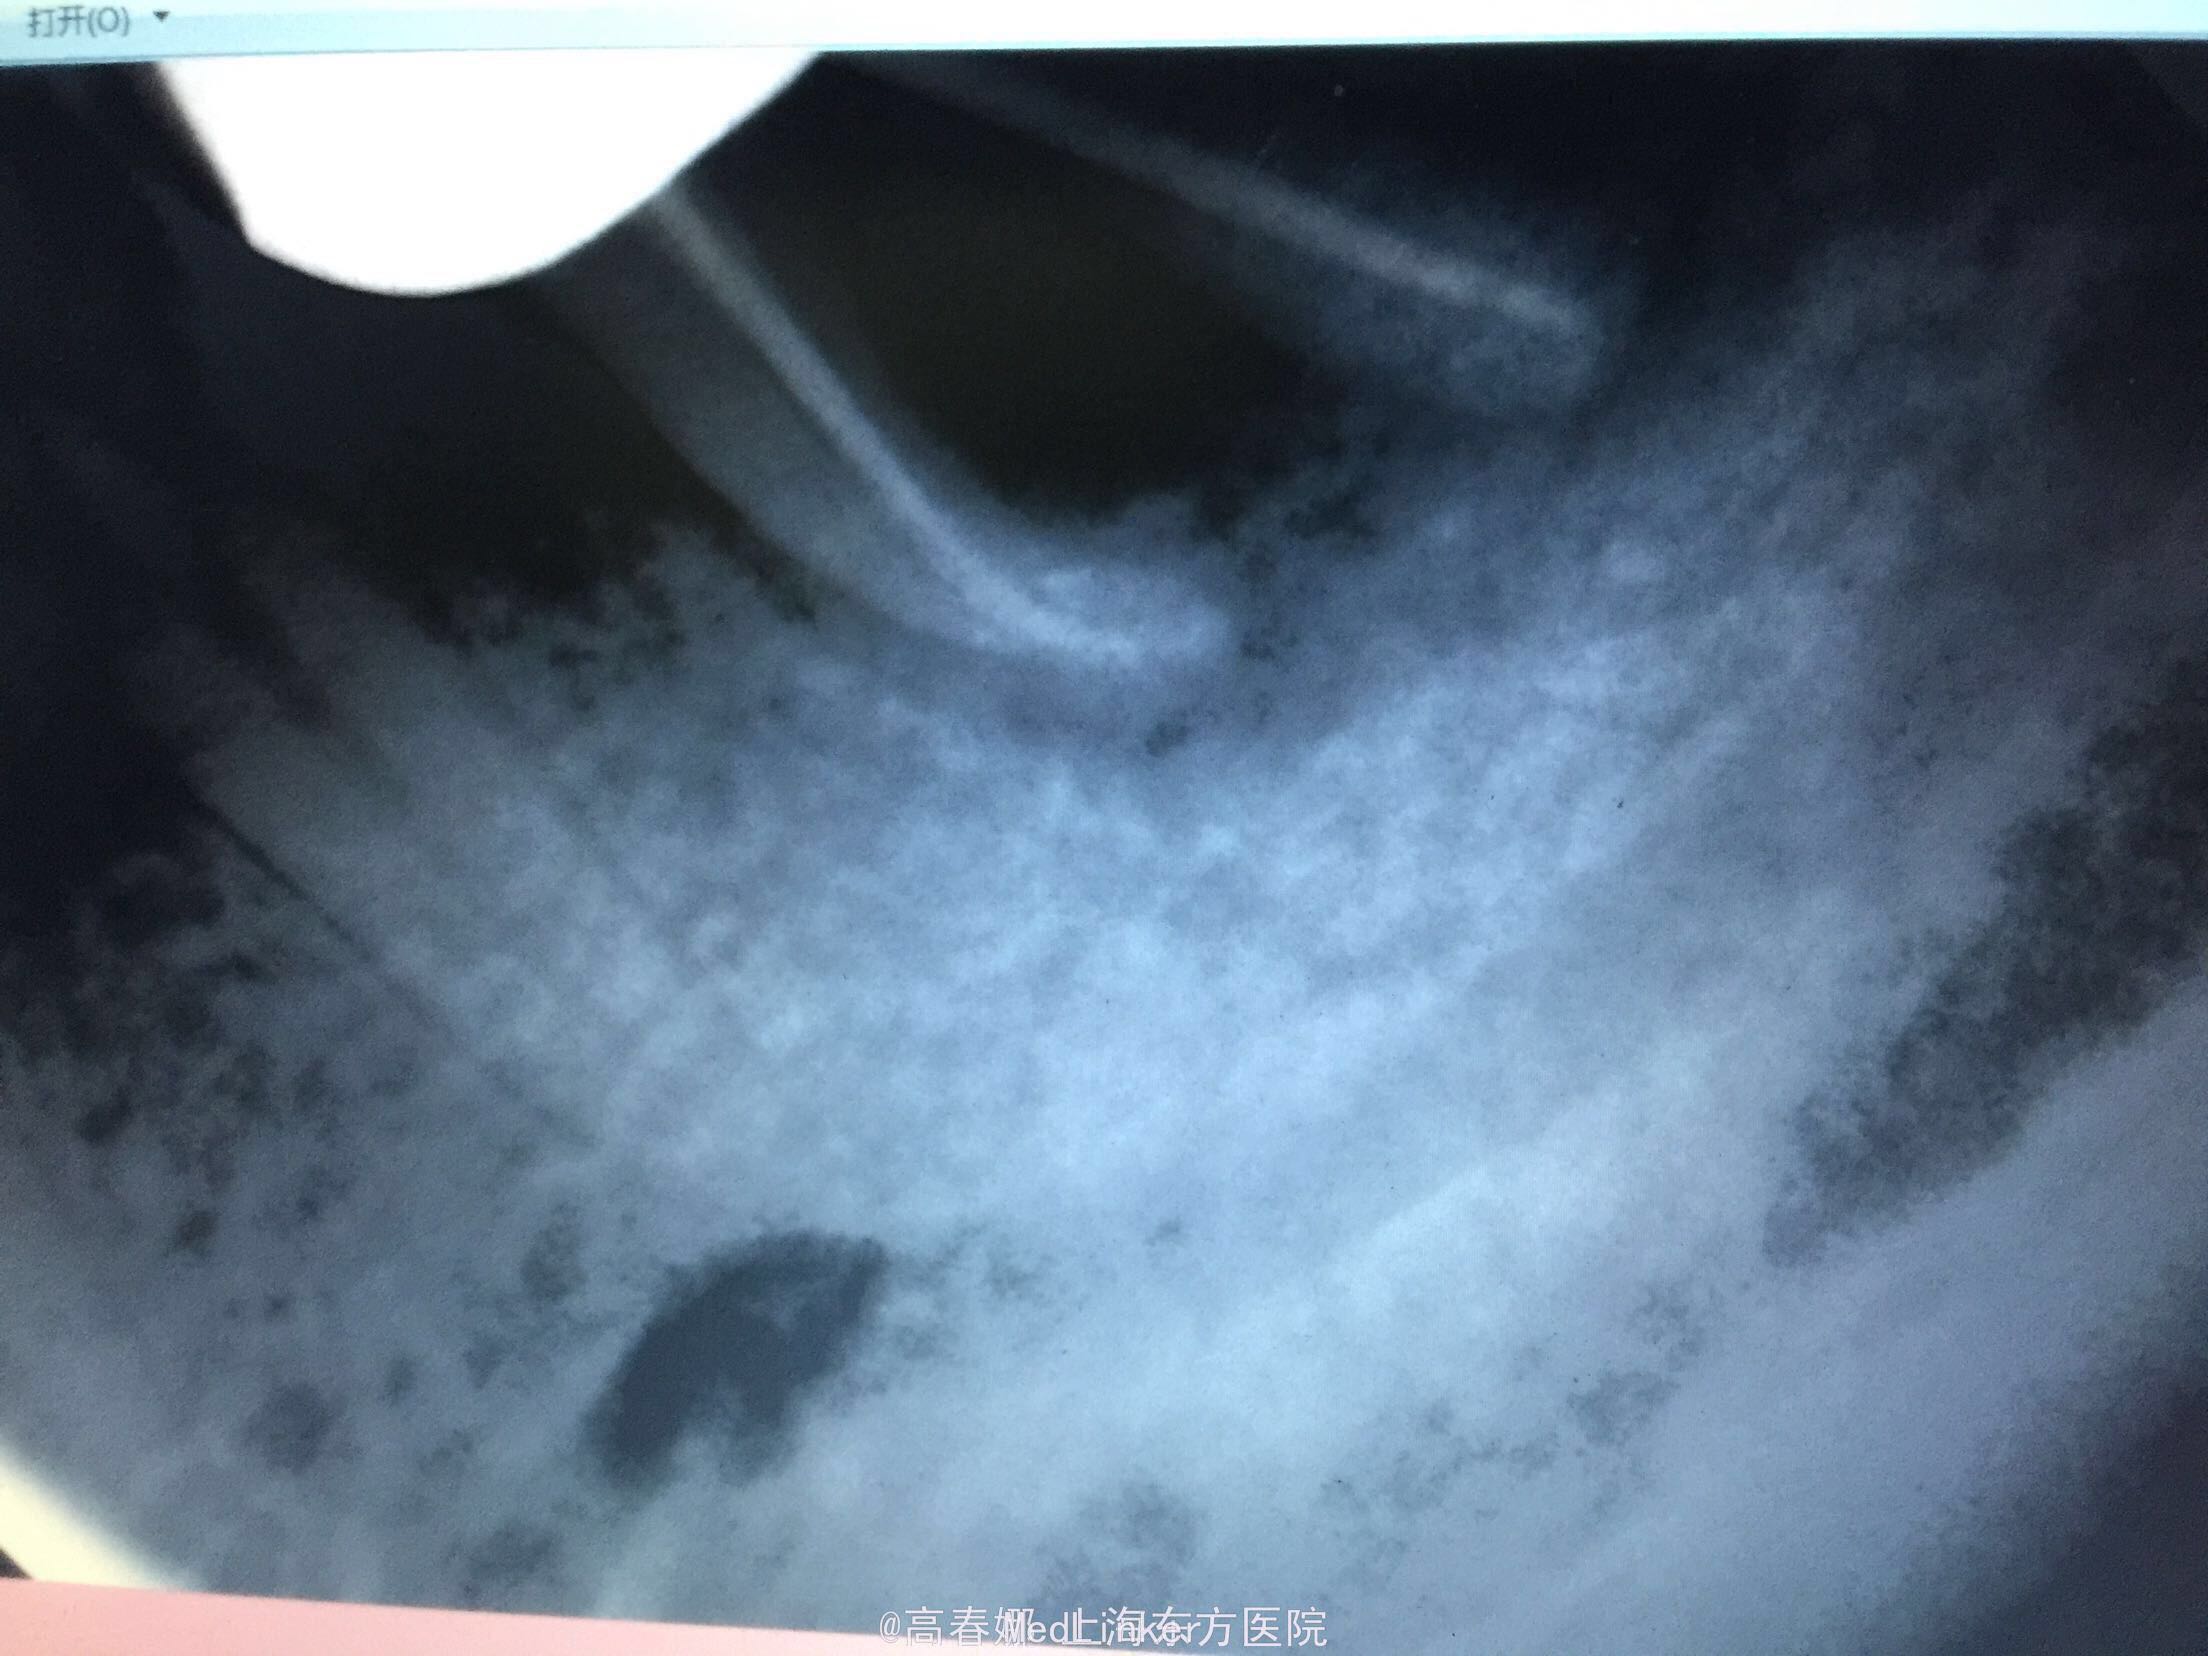

检查:36冠修复,叩诊(+-),松动II度,颊侧牙龈瘘管,牙周袋约3mm,根分叉未探及,冷(-)。 X线示:36根尖区及根分叉区大面积阴影。

随访:三个月复查,牙龈未见明显红肿及瘘管,36扣痛无,松动物。X线示:36根尖及根分叉骨密度增高。